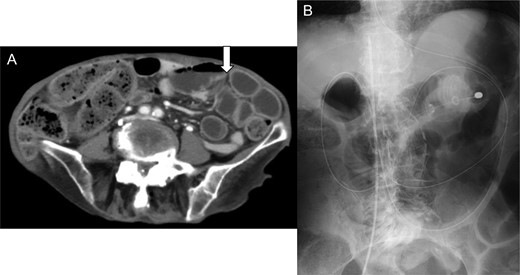

A 76-year-old woman, under the care of a home nurse, had pain on the entire abdomen since the day before presentation to our hospital. She had fever (38.0°C), and her systolic blood pressure dropped to 70 mmHg, and thus, she was referred to our hospital. She was alert and with body temperature of 37.9°C, blood pressure of 83/52 mmHg, heart rate of 103 beats/min, respiratory rate of 30/min, and oxygen saturation of 80% (with 6-L/min mask-to-face ventilation). On physical examination, her abdomen was soft and flat, but she felt tenderness and rebound tenderness on the entire abdomen. Her medical history revealed autoimmune hepatitis controlled with oral steroid, osteoporosis, compression fracture of the spine and spinal canal stenosis, chronic kidney dysfunction, fracture of the left hand and femur, pneumonia, temporomandibular joint myelitis, and cesarean birth with median incision at the lower abdomen. Laboratory test revealed elevation of the inflammation reaction values: white blood cell (WBC), 15 700/μL; C-reactive protein (CRP), 24.0 mg/dL. The blood urine nitrogen (BUN) and serum creatinine values (39.1 and 0.99 mg/dL, respectively) were also elevated. Her urine was purulent and contains rich bacteria (3+) and WBC (3+). Enhanced abdominal computed tomography (CT) showed small intestine dilation, and thus, she was admitted to our hospital with a diagnosis of ileus and septic state, with quick Sequential Organ Failure Assessment Score of 2 points at non-intensive care unit situation (Fig. 1A). An ileus tube was inserted by transnasal endoscopy (Fig. 1B).

(A) Enhanced abdominal computed tomography on admission showing a dilation of the small intestine (white arrow). The patient was diagnosed with ileus state. (B) X-ray of the abdomen revealed an ileus tube and the central venous catheter inserted from the right femoral vein.